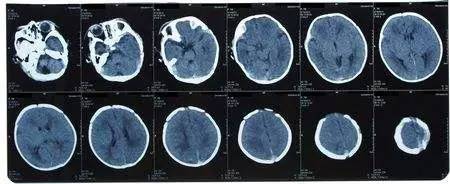

偏头痛的确诊一般靠临床症状,没有哪种仪器检查能够确诊偏头痛。如果怀疑自己患了偏头痛,最好到神经科找有经验的专科医生,把自己头痛的特点详细说明,由医生来判断。有时医生也会给您做一些如经颅多普勒、脑电图、头CT、核磁共振等检查,主要目的是排除器质性疾病。